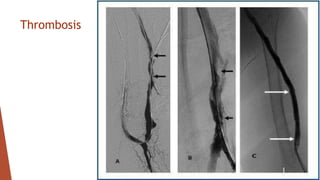

The document discusses various complications that can occur with arteriovenous vascular access for hemodialysis patients. It describes immediate post-surgery complications like hemorrhage and low venous flow. Late complications include infections, aneurysm formation, fistula vein stenosis, congestive heart failure, steal syndrome, ischemic neuropathy, and thrombosis. The document also outlines various physical findings that are associated with different forms of access dysfunction.